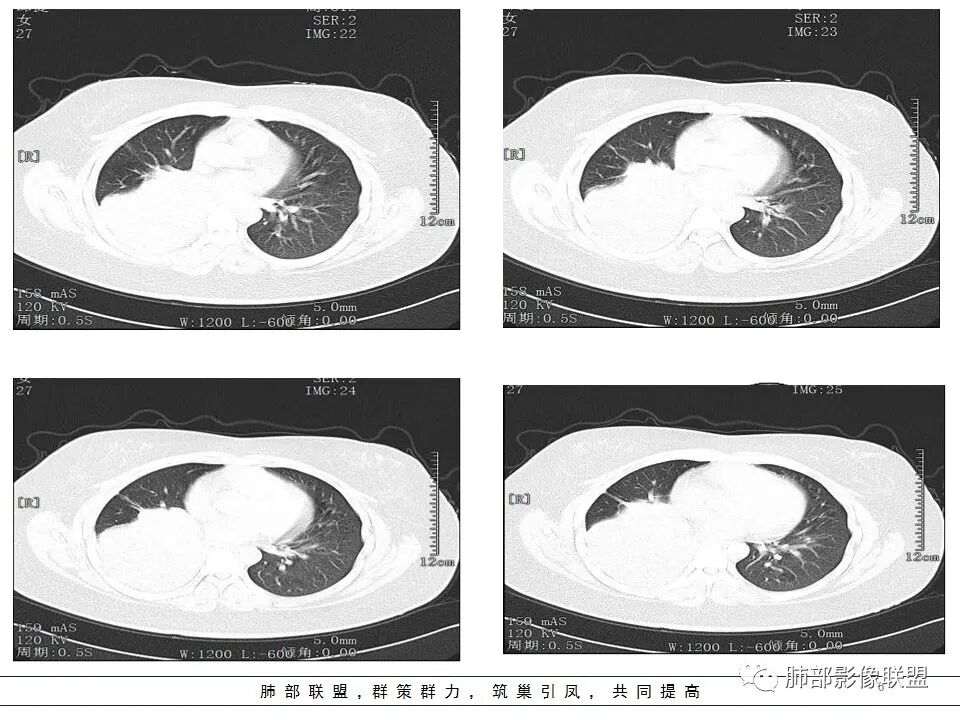

其余区域干净

第一个问题:定位

下叶?还是多叶?

因为这个很关键

例如:上叶、下叶、中叶都受累;中、下叶病变;下叶病变不一样。

上、中、下都有,我要看主支气管,如果主支气管没问题,我不考虑阻塞的问题

中下叶有——中间段支气管

下叶——下叶支气管

我们捋一捋病灶的范围

这是上叶血管

本病例特点是中叶病灶和下叶病灶不一样,支气管腔内的病灶又是怎么样的呢?我们要是有沿支气管重建的冠状位、矢状位会更有利于分析。第一,中叶病灶明显粘液样改变、低密度,且低密度区有占位效应、膨隆,确实要考虑粘液表皮样癌。第二,中叶和下叶支气管显示不出来,但血管显示出来了。中叶病灶血管稀疏、细小,下叶病灶血管粗大、走形正常。朝外肺不张实变,不是单纯的肺不张,肺不张一般体积明显缩小、血管聚拢,该病例肿瘤于其中成分不一样,所以上叶部分病灶考虑为下叶病灶占位效应及膈面向上推压引起,中叶萎缩。综合腔内堵塞、纵隔淋巴结肿大要考虑恶性。

1.年轻女性,发热6天,咳嗽咳痰3天。高热伴腹泻。

2.右肺中下叶大片实性密度影,体积有缩小,密度不均,不均匀强化,前份可疑小范围液性密度区。

5.如此大范围实性密度影,结合高热临床表现,阻塞性肺炎诊断应当是成立的。病灶内梭形液性密度区,未见强化,符合炎性分泌物。